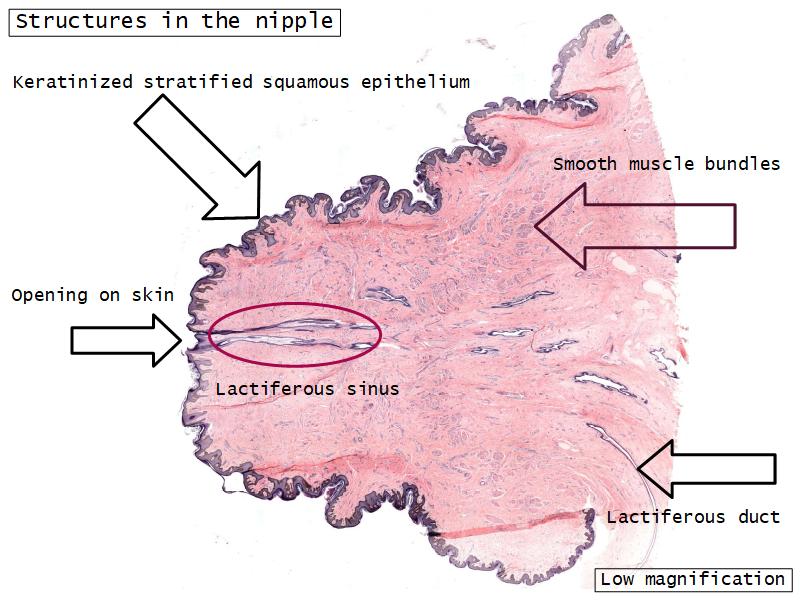

Mammary gland

Write short notes describing the structure of the mammary gland.

(5)

Mammary gland

- Compound tubuloalveolar gland

- 12 - 20 glands

- Each with own lactiferous duct

- Each with own lactiferous sinus

- Opens on skin at apex of nipple

Structures

List the structures and cells found in the mammary gland.

Structures

- Lactiferous sinuses

- Stratified squamous near opening on skin

- Stratified cuboidal other parts

- Lactiferous ducts

- Stratified cuboidal

- Myoepithelial cells

- Underlie lactiferous ducts in most areas

- Basal lamina

- Separate epithelial components from stroma

Morphology

What are the main morphological features of the nipple?

(4)

Morphology

- Covered with skin

- Consists of dense collagenous connective tissue

- Interlaced with smooth muscle fibres

- Contains openings of lactiferous ducts

Skin

- Keratinized stratified squamous epithelium

- Sebaceous glands

Stroma

- Collagenous connective tissue

- Irregular dense connective tissue

- Smooth muscle

- Fibres and bundles

- Lactiferous sinusses

- Stratified cuboidal epithelium